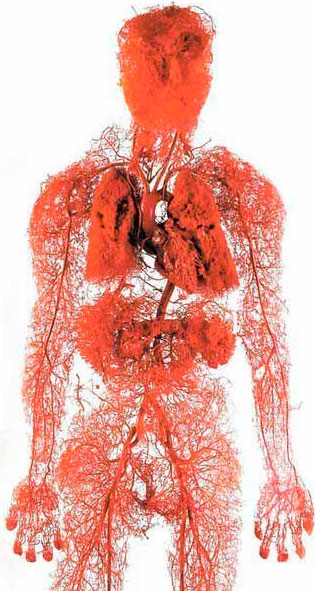

Koji je najveći organ u ljudskom telu? Malo ljudi zna odgovor na ovo. Čak i ljudi koji su studirali medicinu ponekad odgovaraju pogrešno govoreći mozak ili jetra. Neki mudriji mogu reći da je to koža. Zapravo najveći organ u ljudskom telu je vaskularni sistem.

Možemo da obiđemo svet 2,5 puta.

Samo vaskularni sistem jedne osobe bio bi dovoljan za to.

Pokušajte da zamislite. Ako bismo spojili sve vene u ljudskom telu i izmerili ih, dužina bi im bila 100 hiljada kilometara.

Jednostavnije rečeno, dužina ekvatora je 40 hiljada kilometara. Konopac koji se sastoji od jedne ljudske vene može dva puta da omota svet.

Vene nisu samo kanali kroz koje teče krv. To je jedinstven i komplikovan organ. Svaki njihov poremećaj uzrokuje da telo razvije bolest.

Vene su naš izvor energije, životna snaga prolazi kroz njih. Ako se blokira važan čvor, život prestaje.